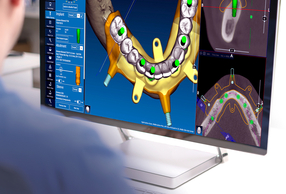

Allineare i file, tracciare la curva panoramica ed identificare i nervi mandibolari sono tutti step indispensabili per la creazione del paziente virtuale fondamentali per la buona riuscita di una chirurgia protesicamente guidata, ma richiedono tempo e un buon training per essere fatti a regola d’arte. Per non parlare delle operazioni di segmentazione di ossa, denti e corone. Il Software RealGUIDE®, a partire dalla versione 5.4, offre numerose funzioni con AI integrata grazie ai potenti algoritmi incorporati.

Con le funzioni AI integrate si passa da 3 ore di lavoro umano a soli 15 minuti di elaborazione automatica. Questi nuovi strumenti ti permettono di ottenere il tuo paziente virtuale in pochi click e con il minimo sforzo:

Più tempo quindi da dedicare al paziente, alle sue terapie, alla pianificazione implantare o alla progettazione di guide chirurgiche e ricostruzioni protesiche.

RealGUIDE® è il primo sistema aperto al mondo che integra applicazioni di imaging 3D, pianificazione implantare e modellazione protesica su dispositivi mobili e cloud e, a breve, sarà anche in versione web!

Niente più scambi di file tra diversi pacchetti software e niente installazioni. Il tuo flusso digitale si gestisce in un unico ambiente di lavoro con RealGUIDE® di 3Diemme ora anche con un aiuto in più!

Allineare i file, tracciare la curva panoramica ed identificare i nervi mandibolari, sono tutti step indispensabili per la creazione del paziente virtuale, fondamentali per la buona riuscita di una chirurgia protesicamente guidata, ma richiedono tempo e un buon training per essere fatti a regola d'arte. Per non parlare delle operazioni di segmentazione di ossa, denti e corone. Dalla versione 5.4, il Software RealGUIDE™ aumenta la quantità di funzioni con AI integrata grazie ai potenti algoritmi sviluppati dal team 3Diemme. Grazie all'AI si passa da 3 ore di lavoro umano a soli 15 minuti di elaborazione automatica. Gli strumenti di intelligenza artificiale integrati ti permetteranno di ottenere il tuo paziente virtuale in pochi click e con il minimo sforzo:

Più tempo quindi da dedicare al paziente, alle sue terapie, alla pianificazione implantare o alla progettazione di guide chirurgiche e ricostruzioni protesiche.

RealGUIDE™ è il primo sistema aperto al mondo che integra applicazioni di imaging 3D, pianificazione implantare e modellazione protesica su dispositivi mobili e cloud. I nuovi strumenti AI non richiedono di inviare file su server esterni online per l'elaborazione e sono inclusi nel costo delle licenze in corso, senza costi aggiuntivi di segmentazione per ogni file elaborato. Niente più scambi di file tra diversi pacchetti software! Il tuo flusso digitale si gestisce in un unico ambiente di lavoro con RealGUIDE™ di 3Diemme, ora anche con un aiuto in più.